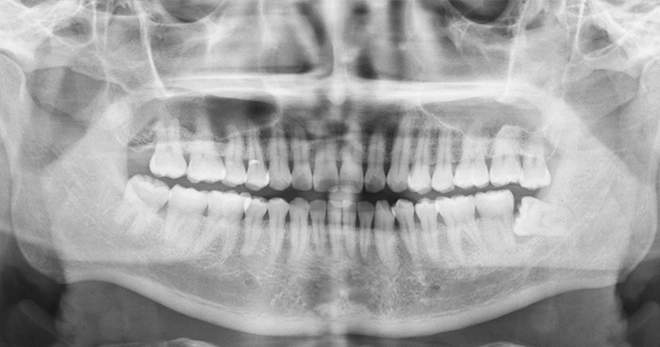

Wisdom teeth, or third molars, are the last set of adult teeth to emerge—usually appearing between the ages of 17 and 25. Some people may have all four, while others may have fewer or none at all.

While some wisdom teeth come through normally, many become impacted (trapped beneath the gum or bone) or misaligned due to limited space in the jaw. These issues can lead to a range of complications, including:

Our team will assess your individual case using digital imaging and a thorough examination to determine the most suitable timing and approach for extraction.